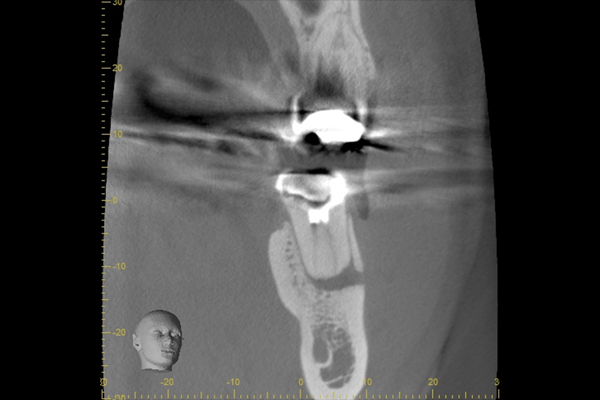

他院で診てもらったが腫れや痛みが変わらないとのことだったので、患歯を見極めることがまずは重要になります。今回は左上の前から5番目の歯が原因と判断しました。診断名は急性根尖性歯周炎。

【担当医所見】

患歯を見極めるためと、状態の悪さをみるため、CTを撮影しました。治療前では上顎洞への大きな炎症が見られます。また、上顎洞底線も無くなっています。また左上の前から4番目の歯の根尖周囲にも透過像が見られます。5番目の歯に関しては根尖が鋭利になっており、根尖性歯周炎によって吸収されたことがわかります。ですので、まず第一の患歯は5番目の歯であるとしました。

治療後3ヶ月経つと上顎洞への炎症も無くなっています。また、上顎洞底線もきれいにみえます。4番目の歯の根尖周囲の透過像もなくなりました。5番目の根尖にまだ透過像がありますが、臨床的症状がないことから、治癒傾向にあるものと判断しました。